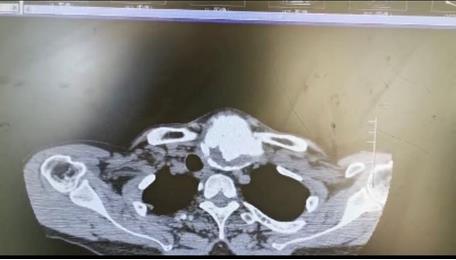

患者朱女士,68歲,頸部包塊呈進(jìn)行性增大50年,來(lái)院后彩超及CT提示左側(cè)甲狀腺腫瘤已經(jīng)超過(guò)10公分并邊緣鈣化,氣管移位較明顯,腫瘤較大屬于罕見,不僅給患者造成心理陰影,還影響了正常生活,偶有憋悶不適,進(jìn)食較大食物感哽咽不適。流動(dòng)醫(yī)院下鄉(xiāng)義診時(shí),發(fā)現(xiàn)包塊已經(jīng)很大了,影響到頸部的活動(dòng)及飲食。醫(yī)生與患者及家屬溝通講解病情,表示我們?nèi)揍t(yī)院能治療。最后患者及家屬抱著試一試的態(tài)度來(lái)到延安大學(xué)咸陽(yáng)醫(yī)院。